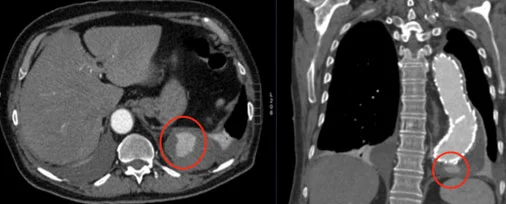

mmagine TC che mostra un endoleak visibile durante il follow-up post-implantazione.

EL Tipo Ib

EL Tipo II